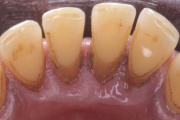

- igemepiir on taandunud (3)

- luu destruktsioon (5)

- hamba kinnitussidemete kadu (3)

- igemepealne hambakivi (5)

- igemealune hambakivi (4)